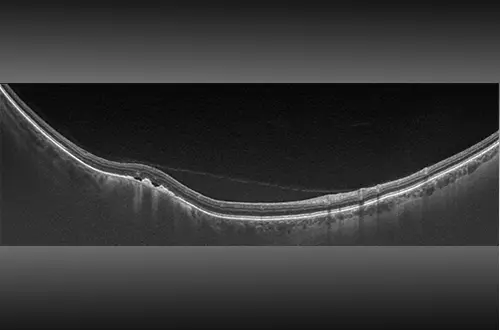

Swept-Source OCT

Swept-source facilitates examination of the retina from vitreous through the choroidal-scleral interface. The SS-OCT and UWF combination produces a 200° single-capture optomap image in less than ½ second and enables guided OCT scanning across the retina and into the far periphery. The image shown is a 23 mm line scan.